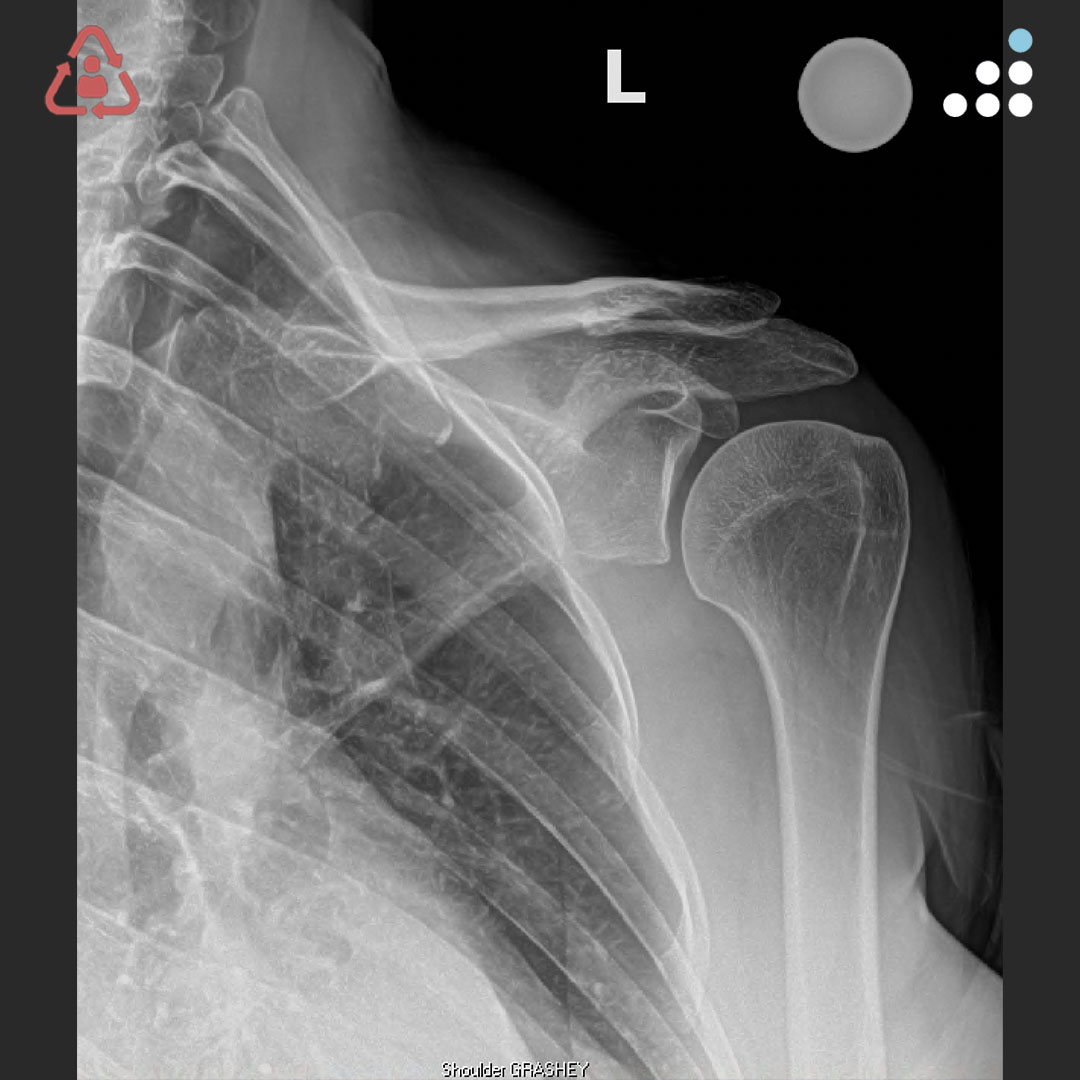

@orthobullets @KPSCALnews @rkh_md @DrMarecek @DeformityDoc @jamesablairMD @FractureDoc @stevemchale @traumaticum @DrFraneNicholas I am concerned about the +Fleck/flake sign. Get MRI or ultrasound to rule out a triceps rupture. If torn, I would perform ORIF and Triceps repair, after restoring the underlying metabolic issues. If the triceps is not torn, then would treat non-operatively.